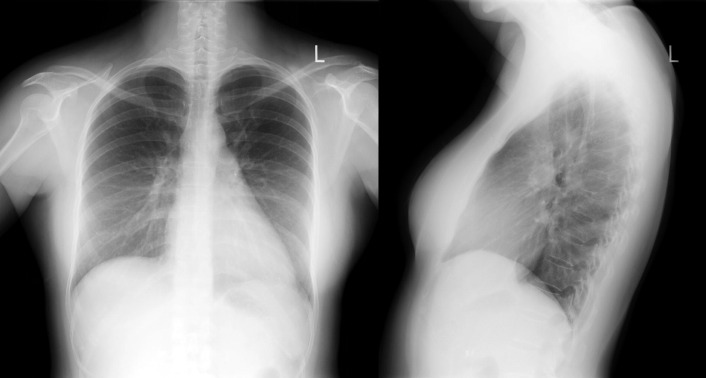

A patent foramen ovale is present in 25% to 30% of the adult population ( Figs. 18-1 to 18-4 ). Any magnitude of shunting across it in normal circumstances is undetectable radiographically. Percutaneous patent foramen ovale closure devices are fairly commonly inserted and are radiographically evident.